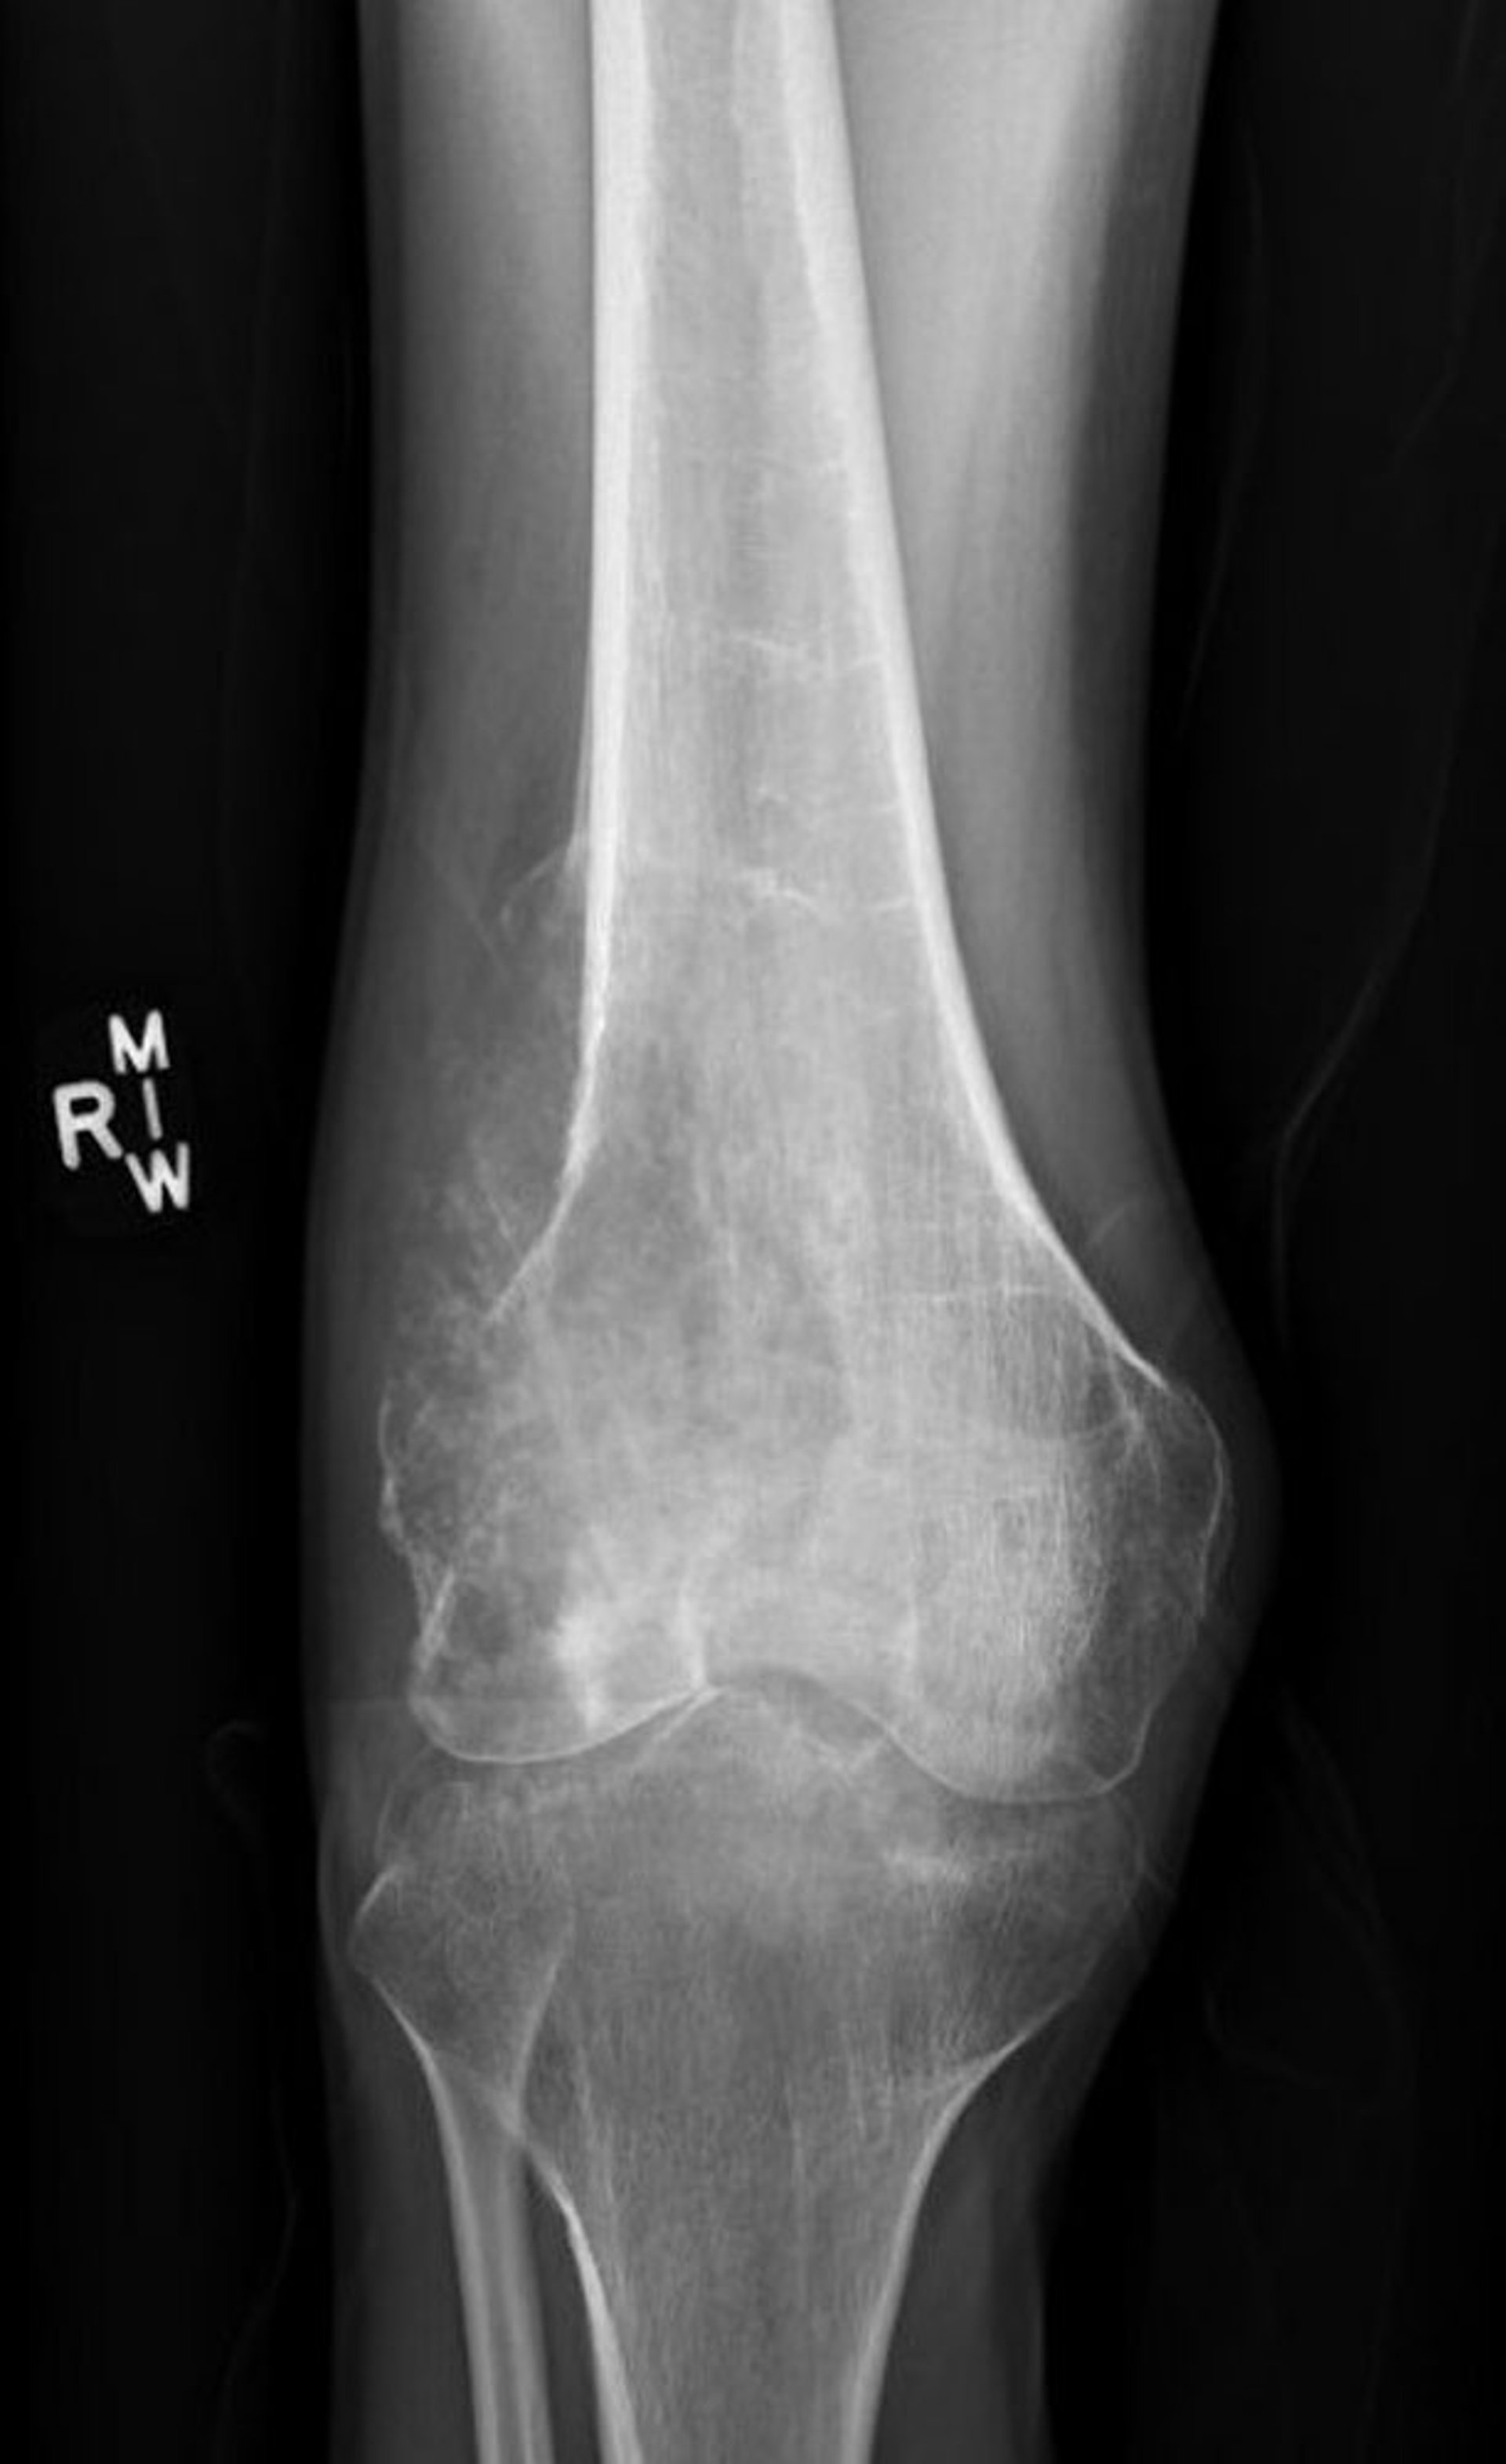

Zur Diagnose des Ewing-Sarkoms werden Röntgenuntersuchungen durchgeführt. Im Röntgenbild können zwar einige Details sichtbar sein, die exakte Tumorgröße ist jedoch mit der Magnetresonanztomographie (MRT) erkennbar. Zur Bestätigung der Diagnose wird eine Biopsie durchgeführt.

Bild mit freundlicher Genehmigung von Dr. med. Michael J. Joyce und Dr. med. Hakan Ilaslan.